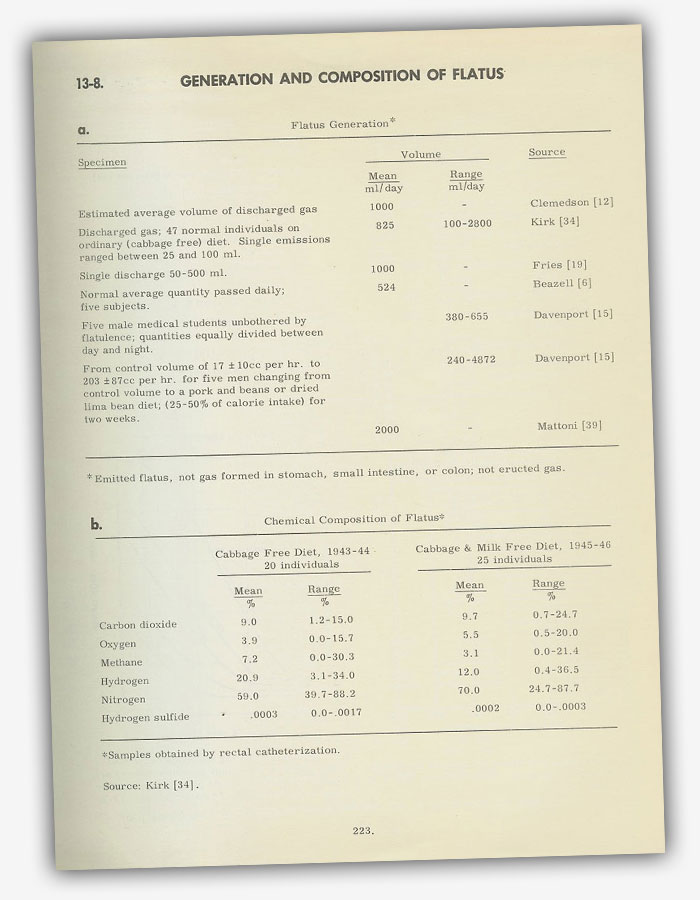

The Chemical Composition of a Fart. Something I Never Knew